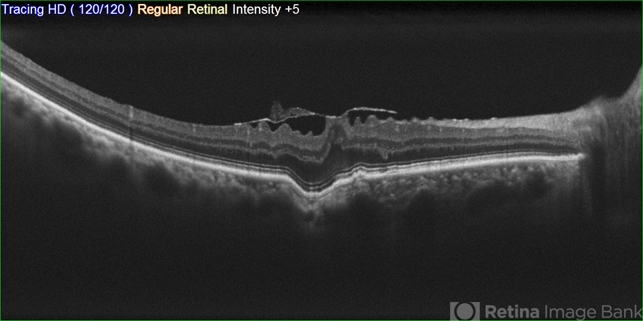

Focal choroidal excavation and Epiretinal membrane

- choroidal excavation, epiretinal membrane (ERM)

- 56 y.o. male complaining of blurred vision.